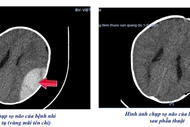

Sau khi được các bác sĩ phẫu thuật loại bỏ khối u, tình trạng sức khoẻ của bệnh nhân Đ.T.R. (Quảng Trị) phục hồi tốt, có thể xuất viện trong những ngày tới.